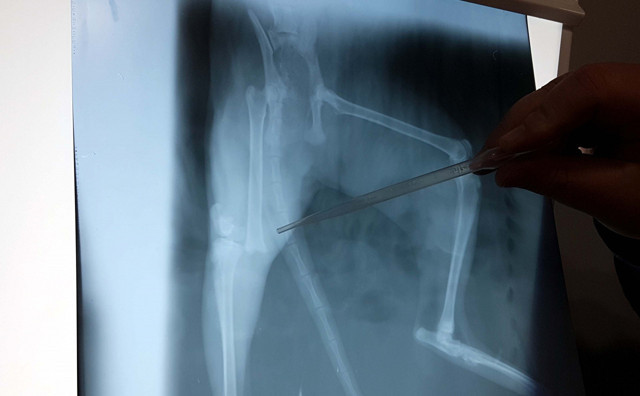

Burada kedinin çekilen röntgen filmi sonucunda diz ekleminde 'femur' kemiğinde kırık tespit edildi. Veteriner hekim Ali Nuri Yiğit ve Veteriner Hekim Ali Laçinbala'nın yaklaşık 1 saat süren başarılı operasyonunda "intrameduller pin" uygulaması yapıldı. Van kedisi tedavisinden kısa bir süre sonra ayaklarının üzerine basarak yürümeye başladı.

Operasyonu gerçekleştiren Veteriner Hekim Ali Nuri Yiğit, çekilen filim sonrasında kırığın düzgün ancak kemiğin çok ayrılmış olduğunu söyleyerek, "Kasları zedelemeden, sinir dokularına zarar vermeden küçük bir enjeksiyonla kemiği yerine getirmeye çalıştık. İntrameduller pin uyguladık ve başarılı oldu. Geçmiş olsun diyoruz" dedi.